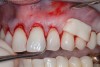

A male patient in his 30s presented for treatment of increasing recession he had had over his lifetime. Upon examination, a complete lack of gingiva on the facial of tooth No. 6 was observed. Although he had about 1.5 mm of gingiva on the facial of tooth No. 7 (Figure 4), both teeth probed to 3 mm. This indicated an absence of attached gingiva on the facial of these teeth in addition to increasing recession.

Fig 4. Patient presented with no gingiva on tooth No. 6 and 1.5 mm of gingiva on tooth No. 7 with increasing gingival recession. Probing of each tooth to 3 mm indicated a lack of attached gingiva.